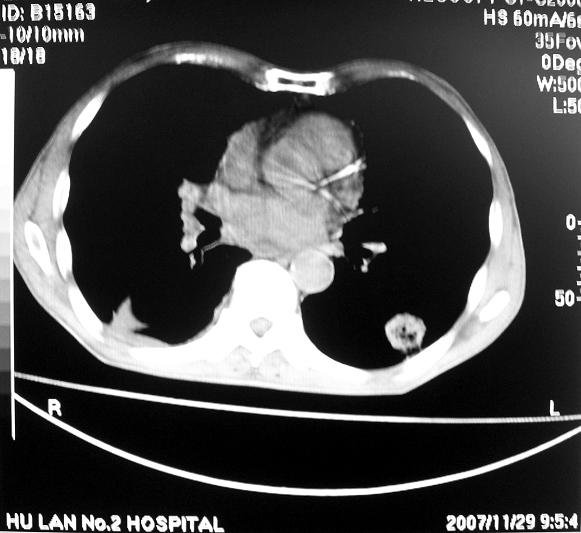

男63岁胸痛来诊

右下肺周围性肺ca并双肺及右侧胸膜转移。[emb6]

右肺病灶前缘不平整,略呈分叶状,其后方胸膜下脂线消失且似有向胸壁浸犯,左下肺球形灶内可见不规则空洞影,余双肺内可见多枚结节影,结合病史支持考虑肺癌肺内转移胸膜转移,便双肺后部病灶倒也是结核好发区域,建议穿刺活检

右下肺周围性肺ca并双肺及右侧胸膜转移。

右下肺周围性肺ca并双肺及右侧胸膜转移。单看病变像炎性假瘤。

右下肺癌伴双肺及胸膜转移。

[quote]以下是引用余辉在2007-12-2 20:29:00的发言:[br]右肺病灶前缘不平整,略呈分叶状,其后方胸膜下脂线消失且似有向胸壁浸犯,左下肺球形灶内可见不规则空洞影,余双肺内可见多枚结节影,结合病史支持考虑肺癌肺内转移胸膜转移。

左肺病灶内可见空泡征及典型的胸膜牵拉征,不排除原发周围型肺癌的可能.